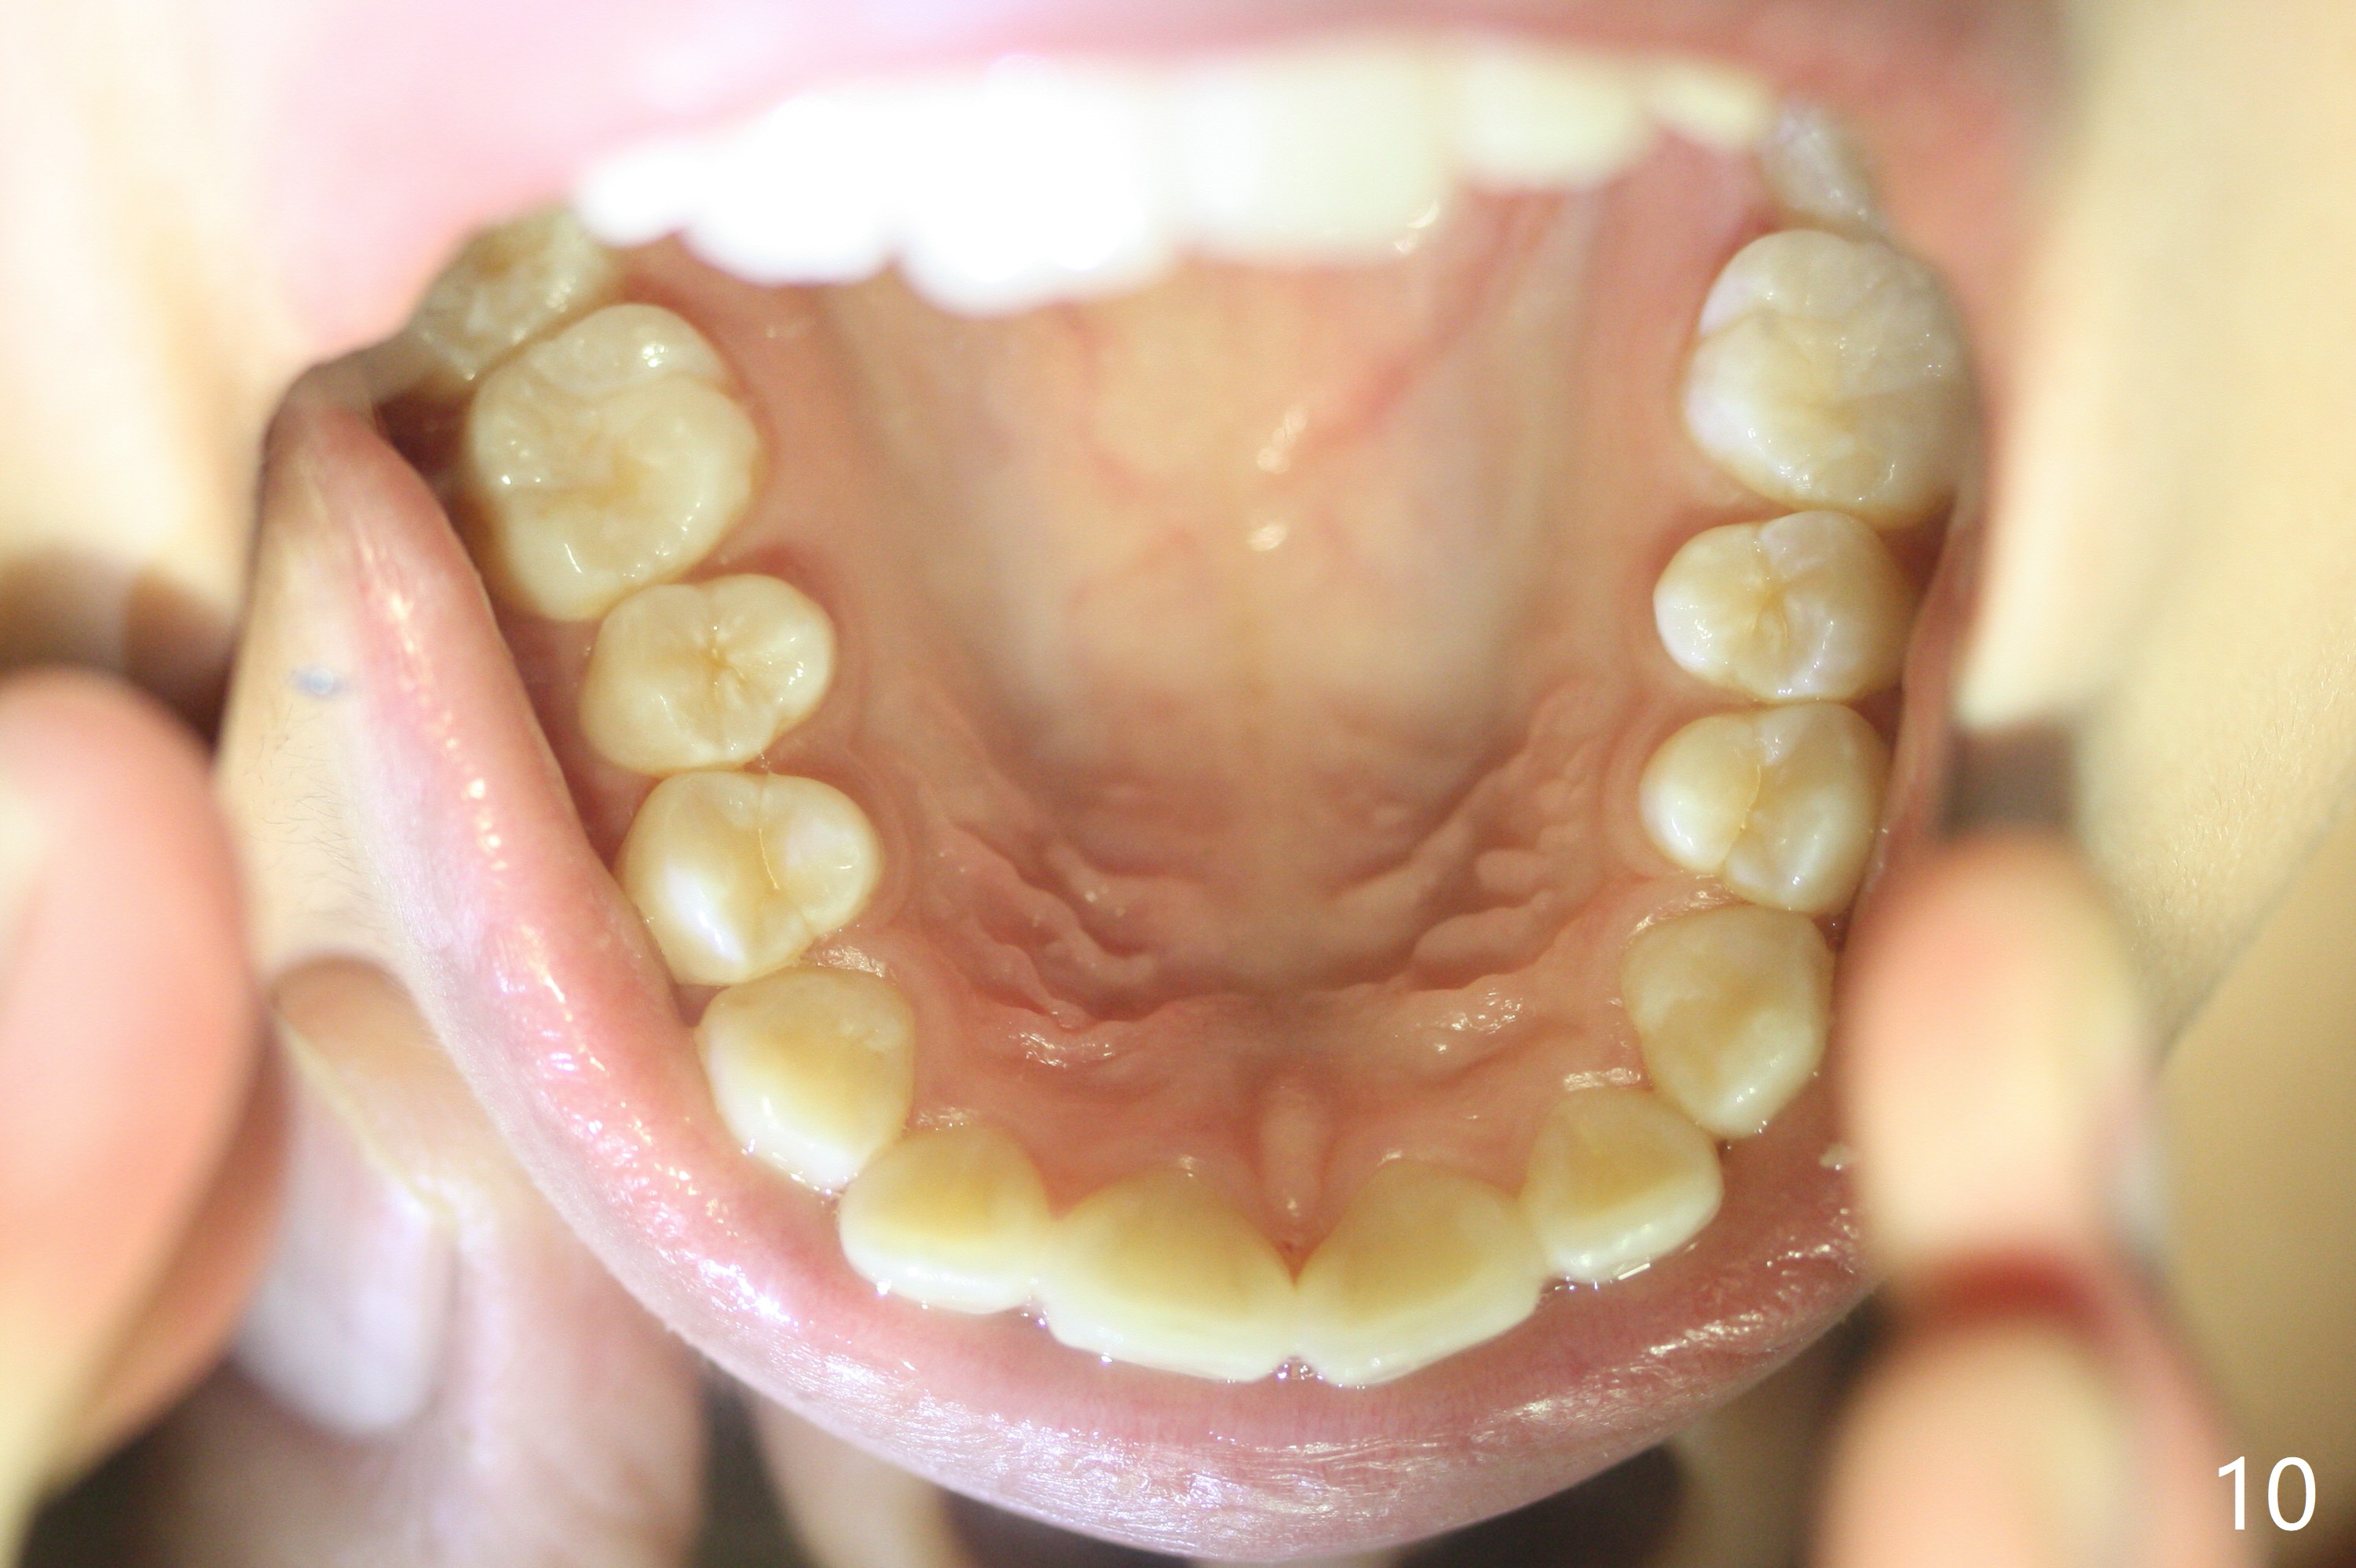

A 15-year-old woman has protrusive lips and retrusive chin (Fig.1-6). Canines and molars have Class I occlusion (Fig.7-9). With 4 bi extraction and 5-7 anchorage (Fig.10-12), 3s will be distalized after 16x16 wires, followed by posted wire retraction of 4 incisors.